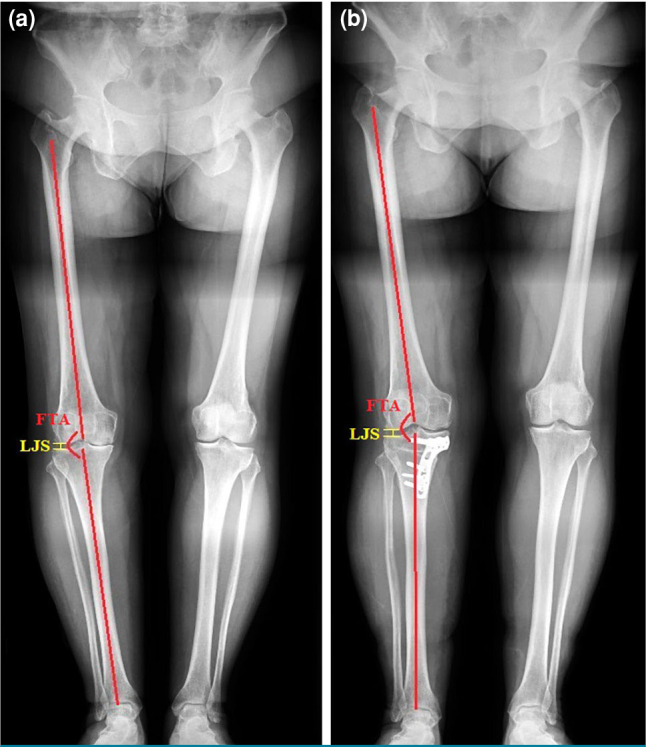

Patients and methods: Between January 2017 and January 2023, a total of 90 patients (47 males, 43 females; mean age: 50.9±5.8 years; range, 40 to 59 years) who underwent PPFR or OWHTO for early-stage medial compartment knee OA were retrospectively analyzed. The patients were divided into two groups based on the surgical technique: Group 1 (n=48) included those who underwent PPFR, while Group 2 (n=42) comprised those treated with OWHTO. Clinical outcomes were evaluated using the Visual Analog Scale (VAS) and the Western Ontario and McMaster Universities Osteoarthritis Index (WOMAC). Radiographic measurements included femorotibial angle (FTA) and lateral joint space (LJS).

Results: Both procedures demonstrated a significant improvement in function and pain. The mean postoperative FTA change was greater in the OWHTO group (7.69±1.35°) compared to the PPFR group (2.87±1.24°, p=0.001). The mean LJS changes were not statistically significant between the groups. Postoperative WOMAC and VAS scores improved in both groups, indicating no significant difference. Minor complications included transient peroneal nerve symptoms in the PPFR group, which resolved spontaneously at three months postoperatively.